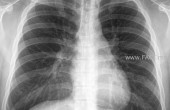

Ууушгины рентген зураг авдаг эмнэлгүүдийн ачаалал ч эрс ихэссэн байна.

Тухайлбал зураг авахуулахад 27-45 мянган